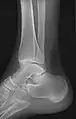

• Ankle - AP/Mortice and Lateral

• Calcaneum - Axial and Lateral

Certain suspected conditions require specific projections. For example, skeletal signs of rickets are seen predominantly at sites of rapid growth, including the proximal humerus, distal radius, distal femur and both the proximal and the distal tibia. Therefore, a skeletal survey for rickets can be accomplished with anteroposterior radiographs of the knees, wrists, and ankles.[20]